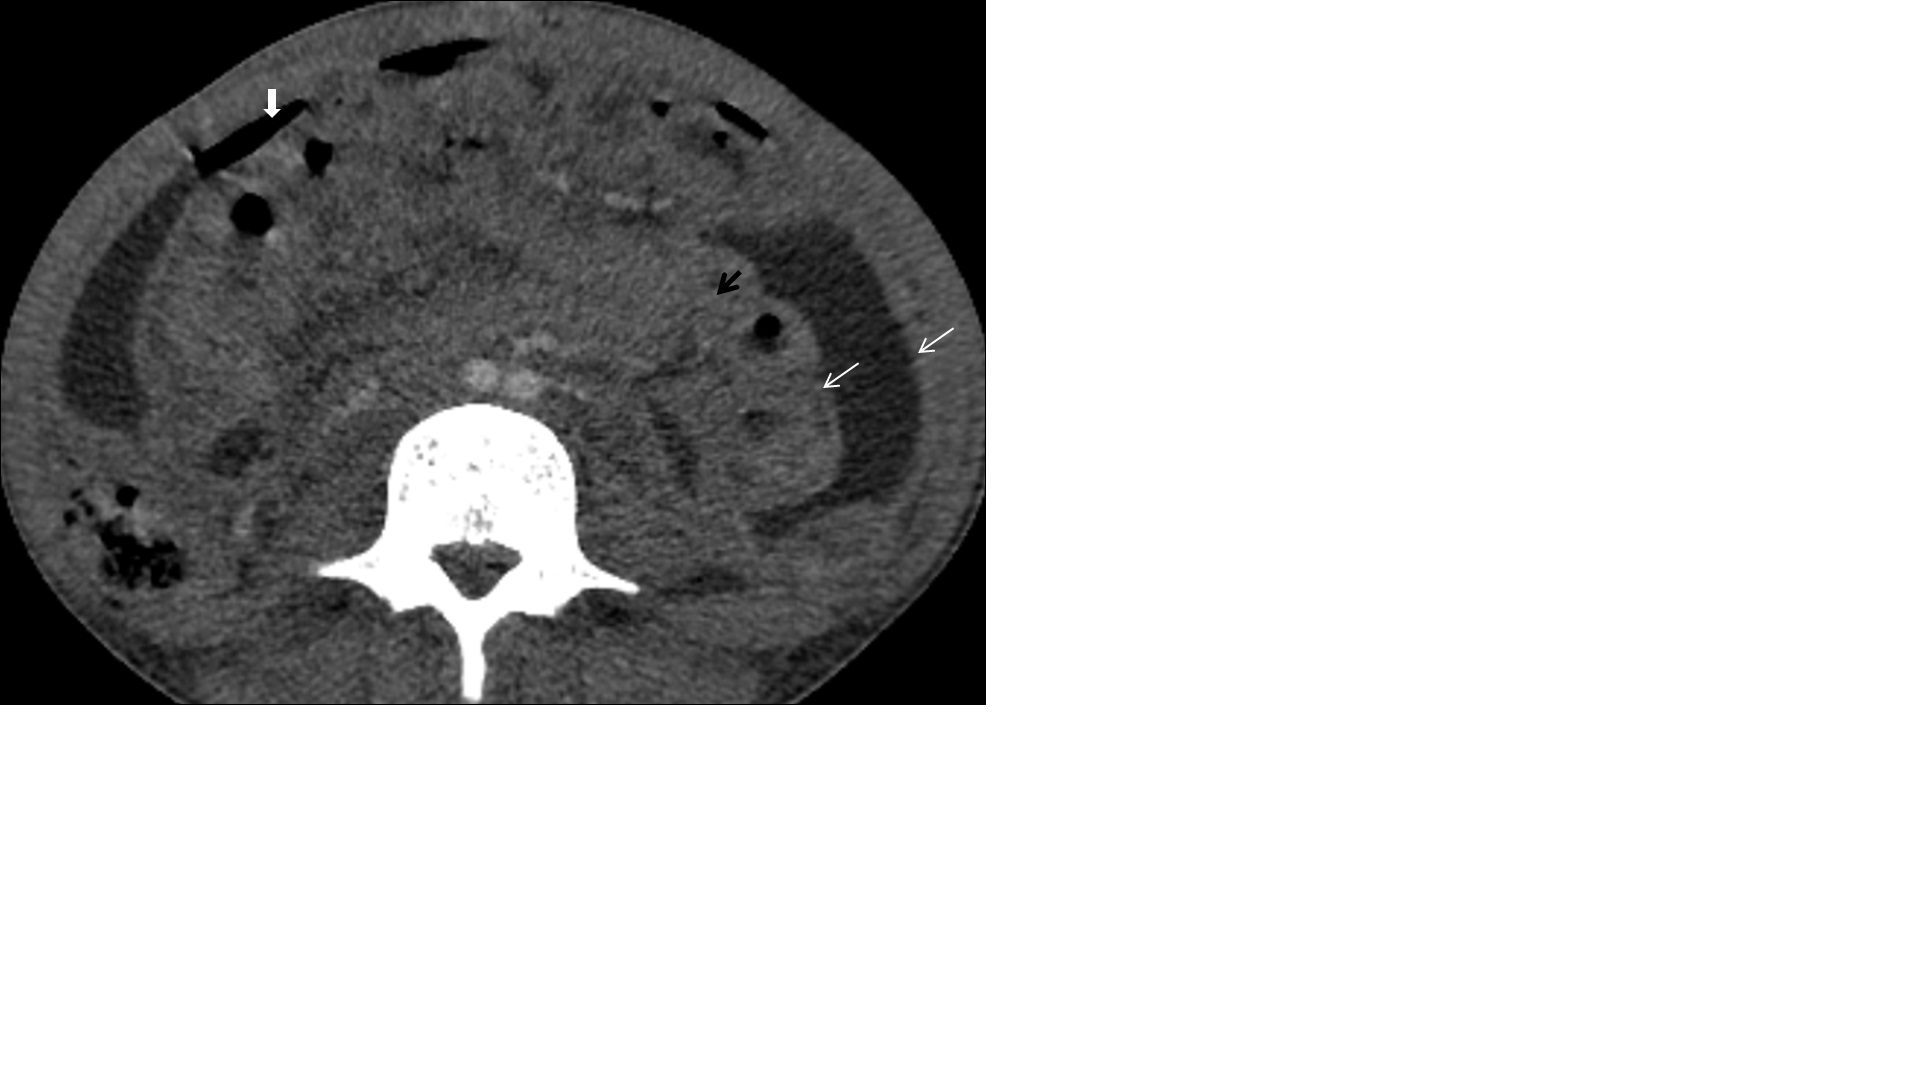

Pancreatic tuberculosis

Isolated tuberculosis of the pancreas is rare, even in countries with a high prevalence of tuberculosis. Pancreatic tuberculosis represents solitary or multiple lesions with multiple necrotic areas. It usually occupies the pancreatic body or head, (Figure 9A,9B) and peripancreatic lymphadenopathy can also be found. The cystic component appears hypoechoic (sometimes hypo-isoechoic) on ultrasound and hypodense on CT scan [9].

Figure 9: (A,B) A 30 years old male patient with constant and chronic vague pain in the epigastric region undergone a contrastenhanced computed tomography of abdomen. The axial and reformatted coronal plane images from the venous phase show a bulky pancreas having intraparenchymal collections (white arrows), peripancreatic fat stranding (thick white arrows) and enlarged lymph nodes (black arrow). It was later diagnosed as pancreatic tuberculosis on fine-needle aspiration from the cystic component. Standard antituberculous therapy involving at least four drugs remains the cornerstone of the treatment. Therefore, the patient has been on ATT for the last three months.